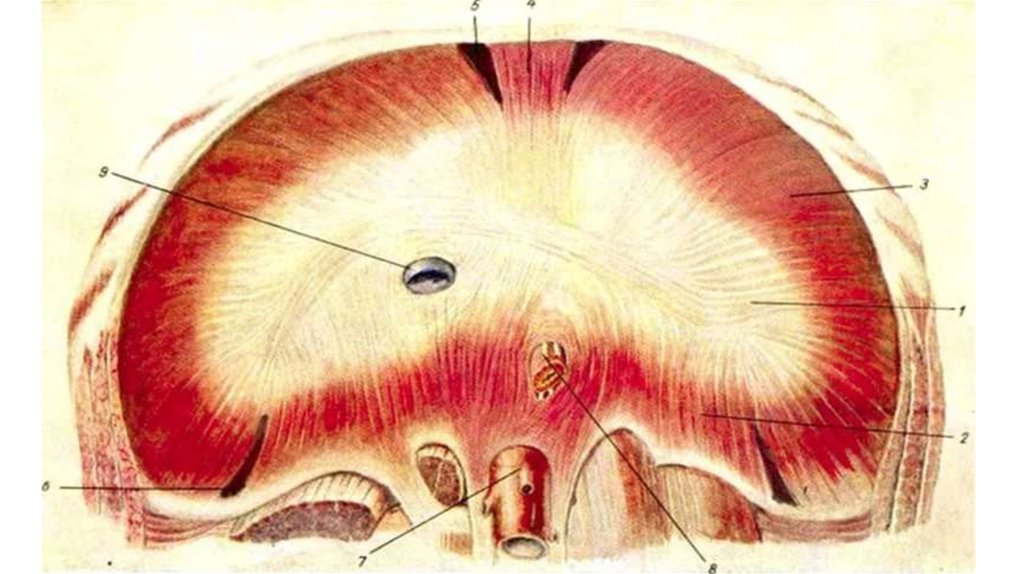

Анатомия диафрагмы и треугольника Бохдалека

Раздел: Визуальный дайджест